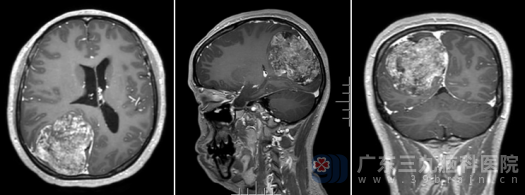

入院后,我院神经外十科团队为陈女士安排了详细的术前检查。术前的头颅MR显示:右侧顶枕部颅骨内板下可见范围约57×45×70mm的团块状不均匀长T1长T2异常信号影,增强后可见明显强化,结合影像学特征,考虑“脊索样脑膜瘤”可能性大。

术前MR

面对这一较大的颅内肿瘤,且肿瘤位置特殊,临近运动、感觉、视力等重要脑功能区,手术难度和风险极高。神经外十科团队迅速组织了术前讨论,制定了周密的手术方案,力求在最大限度保护神经功能的前提下,将肿瘤完整切除。